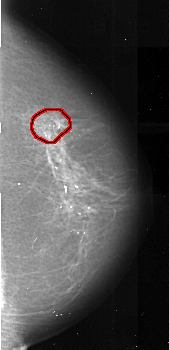

ics_version 1.0 filename A-1021-1 DATE_OF_STUDY 18 11 1993 PATIENT_AGE 59 FILM FILM_TYPE REGULAR DENSITY 2 DATE_DIGITIZED 6 1 1998 DIGITIZER DBA 21 SEQUENCE LEFT_CC LINES 5401 PIXELS_PER_LINE 2641 BITS_PER_PIXEL 16 RESOLUTION 42 NON_OVERLAY LEFT_MLO LINES 5491 PIXELS_PER_LINE 2611 BITS_PER_PIXEL 16 RESOLUTION 42 NON_OVERLAY RIGHT_CC LINES 5236 PIXELS_PER_LINE 2521 BITS_PER_PIXEL 16 RESOLUTION 42 OVERLAY RIGHT_MLO LINES 5491 PIXELS_PER_LINE 2491 BITS_PER_PIXEL 16 RESOLUTION 42 OVERLAY |

FILE: A_1021_1.RIGHT_MLO.OVERLAY TOTAL_ABNORMALITIES 1 ABNORMALITY 1 LESION_TYPE MASS SHAPE ARCHITECTURAL_DISTORTION MARGINS SPICULATED ASSESSMENT 4 SUBTLETY 3 PATHOLOGY MALIGNANT TOTAL_OUTLINES 1 BOUNDARY |

FILE: A_1021_1.RIGHT_CC.OVERLAY TOTAL_ABNORMALITIES 1 ABNORMALITY 1 LESION_TYPE MASS SHAPE ARCHITECTURAL_DISTORTION MARGINS SPICULATED ASSESSMENT 4 SUBTLETY 3 PATHOLOGY MALIGNANT TOTAL_OUTLINES 1 BOUNDARY |